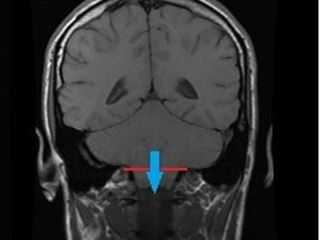

Жалобы, клиническая картина и результаты обследования. Пациентка Г., 16 лет, обследовалась в связи с жалобами на упорные интенсивную инвалидизирующую головную боль и боли в шейно-затылочной области в течение 2 лет. Кроме этого, родственники наблюдали у больной два приступа генерализованных тонических судорог с отключением сознания; электроэнцефалографические данные не подтверждали эпилепсию. Офтальмофундоскопия не выявила признаков внутричерепной гипертензии. При МРТ-обследовании выявлена клиновидная деформация миндаликов мозжечка с их смещением на 17 мм ниже большого затылочного отверстия; гидроцефалии, внутричерепных объемных образований или сирингомиелии не наблюдалось (рис. 1, а). Пациентка госпитализирована для хирургического лечения с диагнозом аномалия Киари-1. При госпитализации в неврологическом статусе имел место спонтанный горизонтальный нистагм, других объективных симптомов не было.

Рис. 1. Данные МРТ и КТ до и после операции. а — МРТ головного мозга до операции: видна клиновидная деформация миндаликов мозжечка и их дислокация в большое затылочное отверстие ниже уровня дужки С1 позвонка; б, в — КТ головного мозга спустя 12 ч после операции: видно, что новое положение костного лоскута (указан желтой стрелкой) позволяет увеличить диаметр большого затылочного отверстия и объем задней черепной ямки; г — МРТ спустя 3 мес после операции: миндалики мозжечка занимают нормальное положение, виден просвет большой затылочной цистерны, нет признаков псевдоменингоцеле.